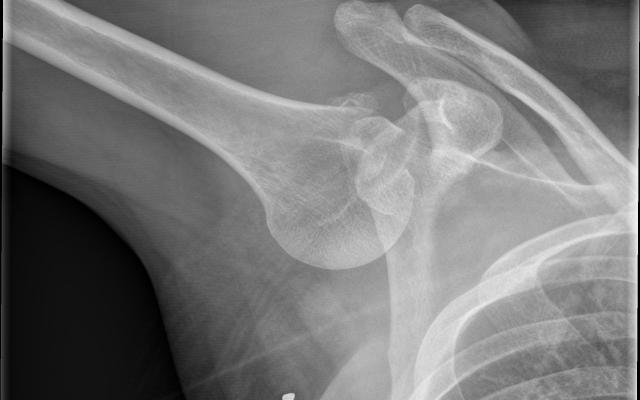

Dit artikel is alleen beschikbaar als PDF.Lees de PDF Artikelinformatie 10 juni 1927 Citeer dit artikel als Ned Tijdschr Geneeskd. 1927;71:2684-92 Heb je nog vragen na het lezen van dit artikel? Check onze AI-tool en verbaas je over de antwoorden. ASK NTVG Ook interessant Beeldquiz Een man met opgeheven bovenarm Diagnose in beeld Een man met opgeheven bovenarm Mededelingen Het therapeutisch monsterverbond opgeheven Meer gerelateerd … Reacties Login om een reactie te plaatsen